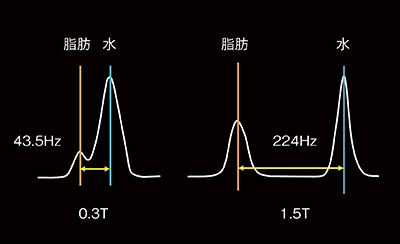

3.脂肪抑制(図3)

CHESS法による脂肪抑制は,水と脂肪の共鳴周波数の違いを利用して,選択的に脂肪信号を抑制しますが,この共鳴周波数は静磁場強度と比例して差が大きくなります。静磁場強度が低いと水と脂肪の周波数が近いため,脂肪の周波数のみをねらってパルスを打つことが難しくなります。そこで,STIRやDIXON法を用いることで安定した脂肪抑制が可能になります。静磁場強度が高い超電導磁石タイプは,このほかにも水励起(water excitation)法なども可能となり,条件に合わせて多彩な脂肪抑制が可能です。

図3 水と脂肪の共鳴周波数の違い